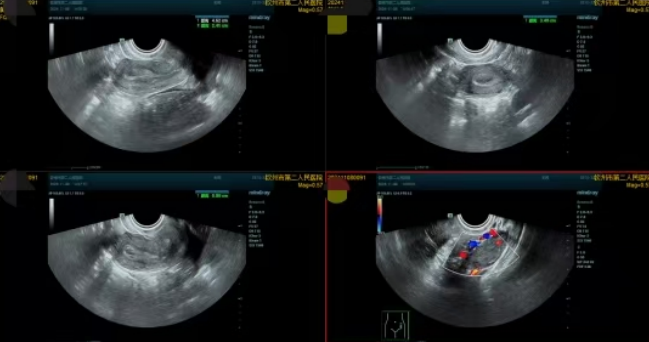

▲子宫内膜息肉患者超声所见